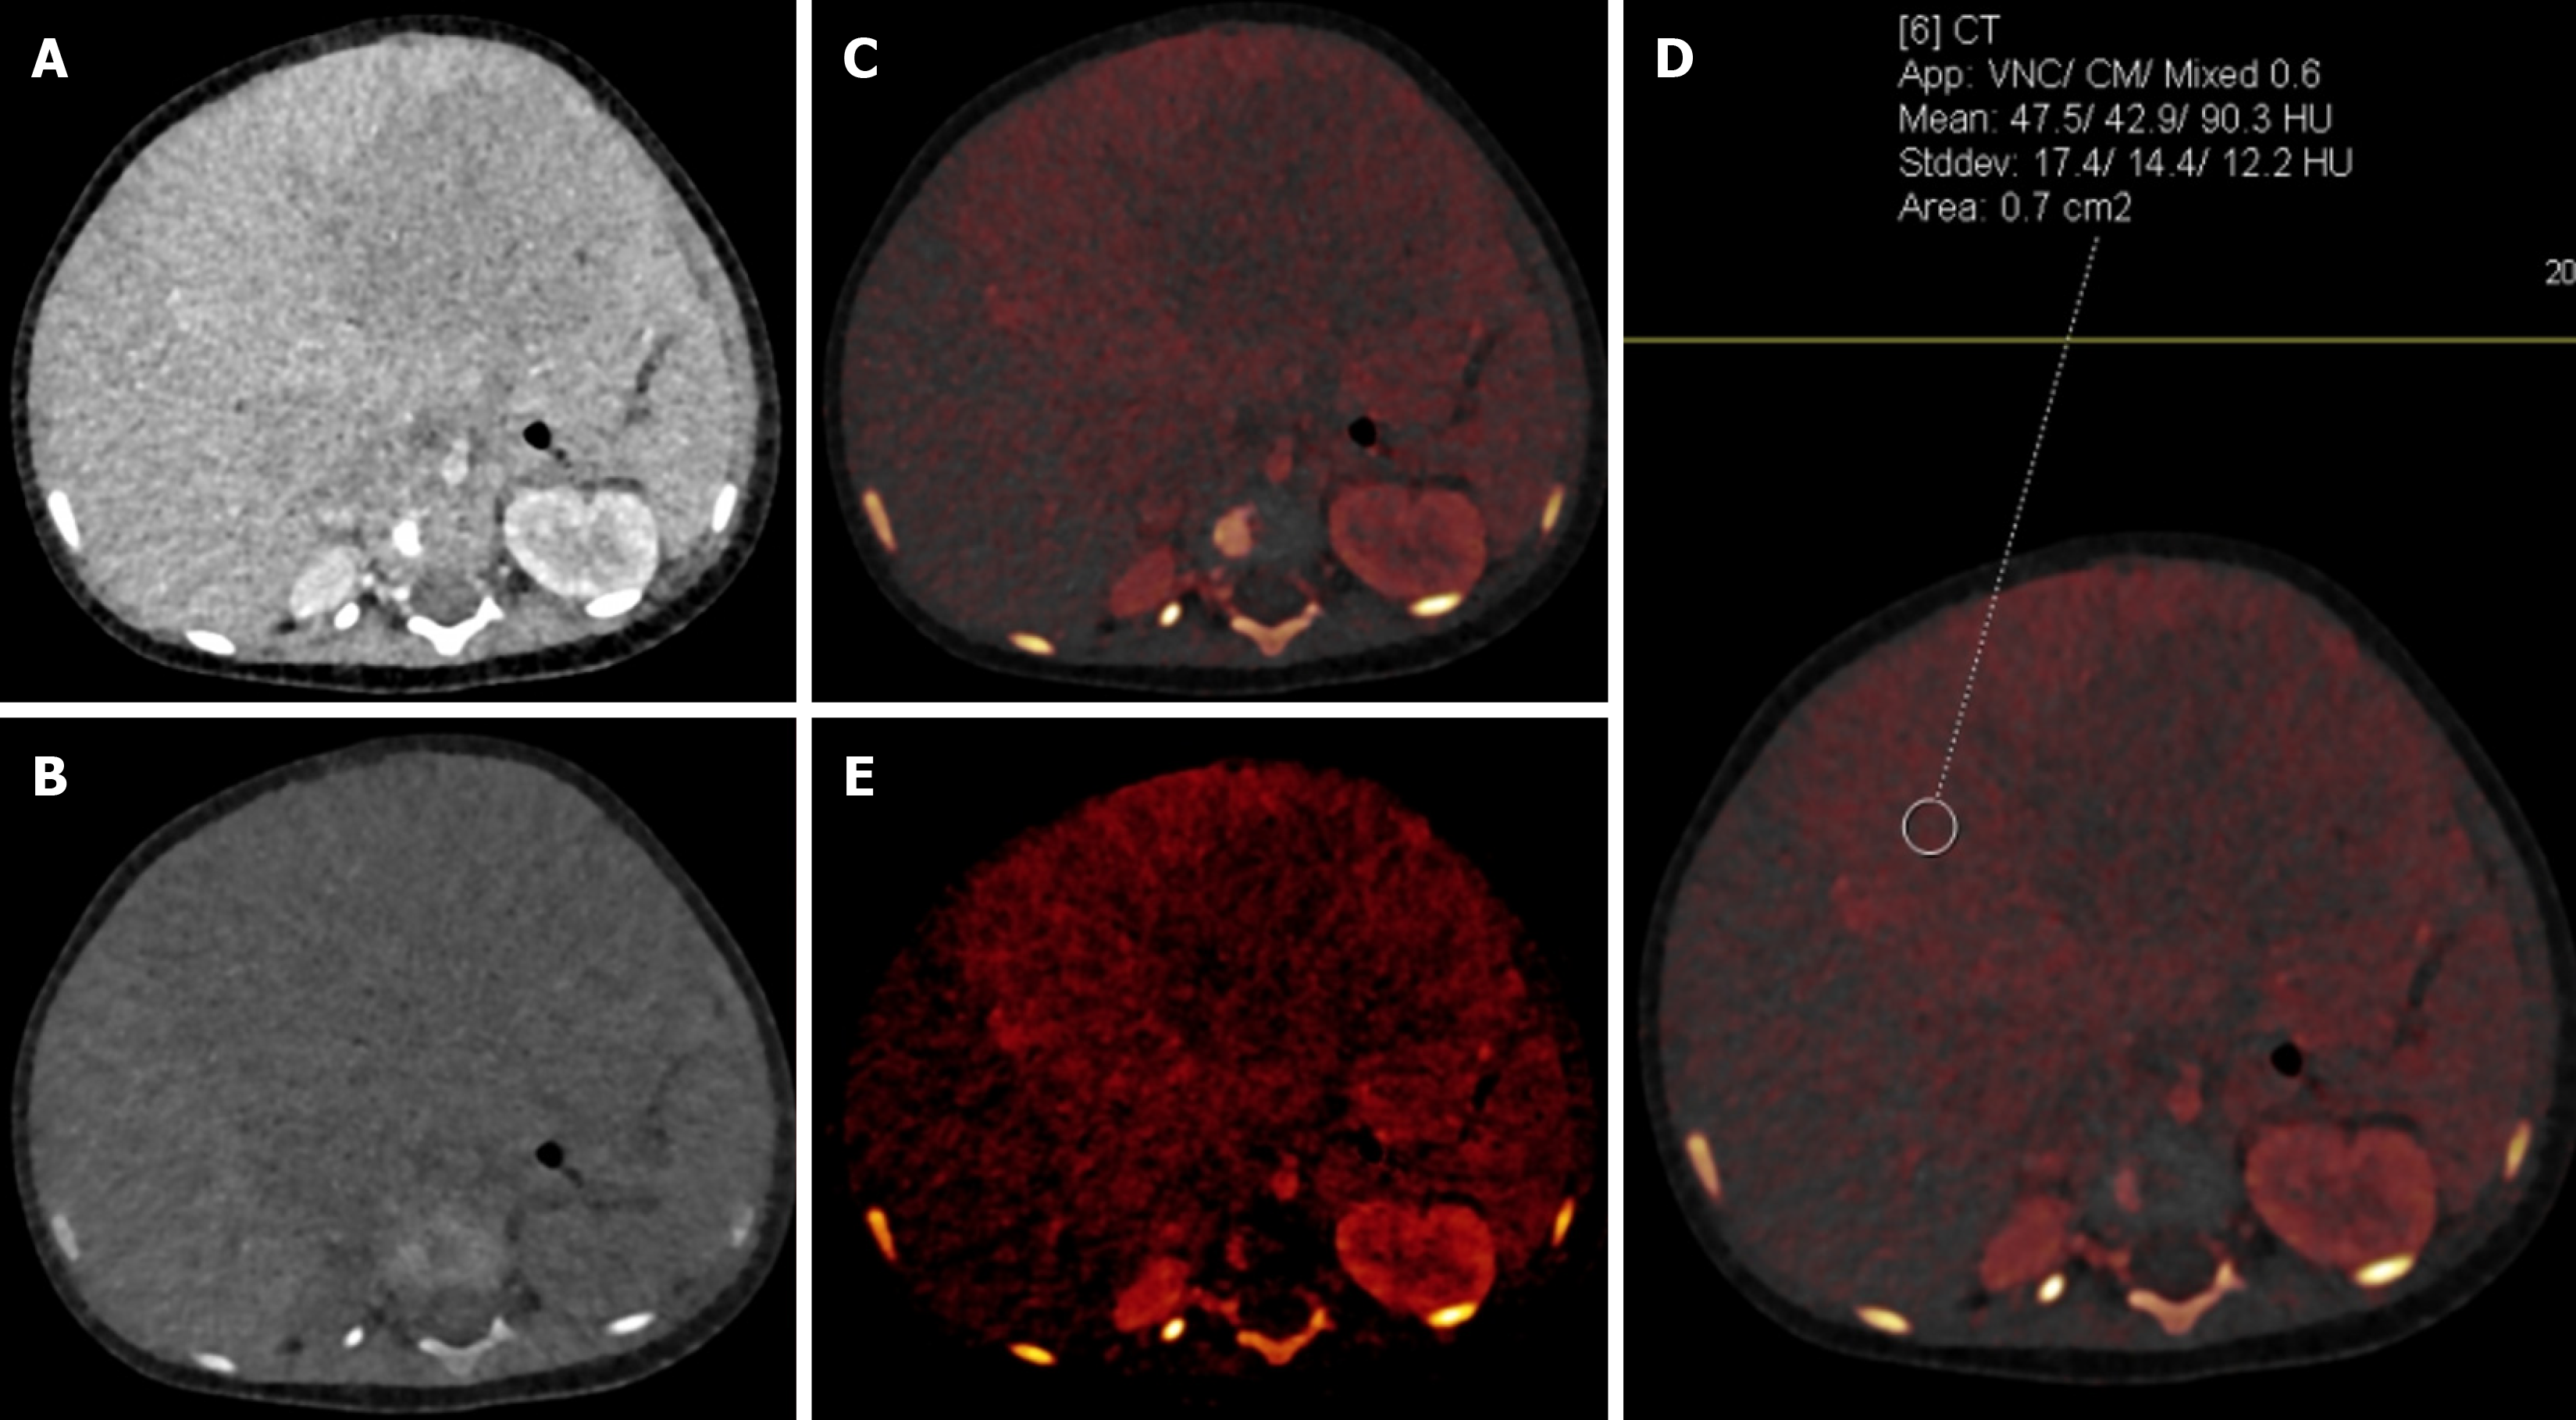

Figure 14 An 11-month-old male with hepatoblastoma.

A: Blended contrast-enhanced axial image showed a large isodense mass in the liver with poor demarcation of the mass with the adjacent liver due to minimal enhancement; B: Virtual non-contrast image showed no evidence of calcification/fat/hemorrhage within the lesion; C and D: Iodine overlay images showed iodine uptake in the periphery of the mass with attenuation on the virtual non-contrast image being 475 Hounsfield units and on the blended image being 903 Hounsfield units, suggesting significant enhancement that was not well appreciated on the blended image; E: Iodine-specific image showed the iodine content in the periphery of the mass to a better advantage.